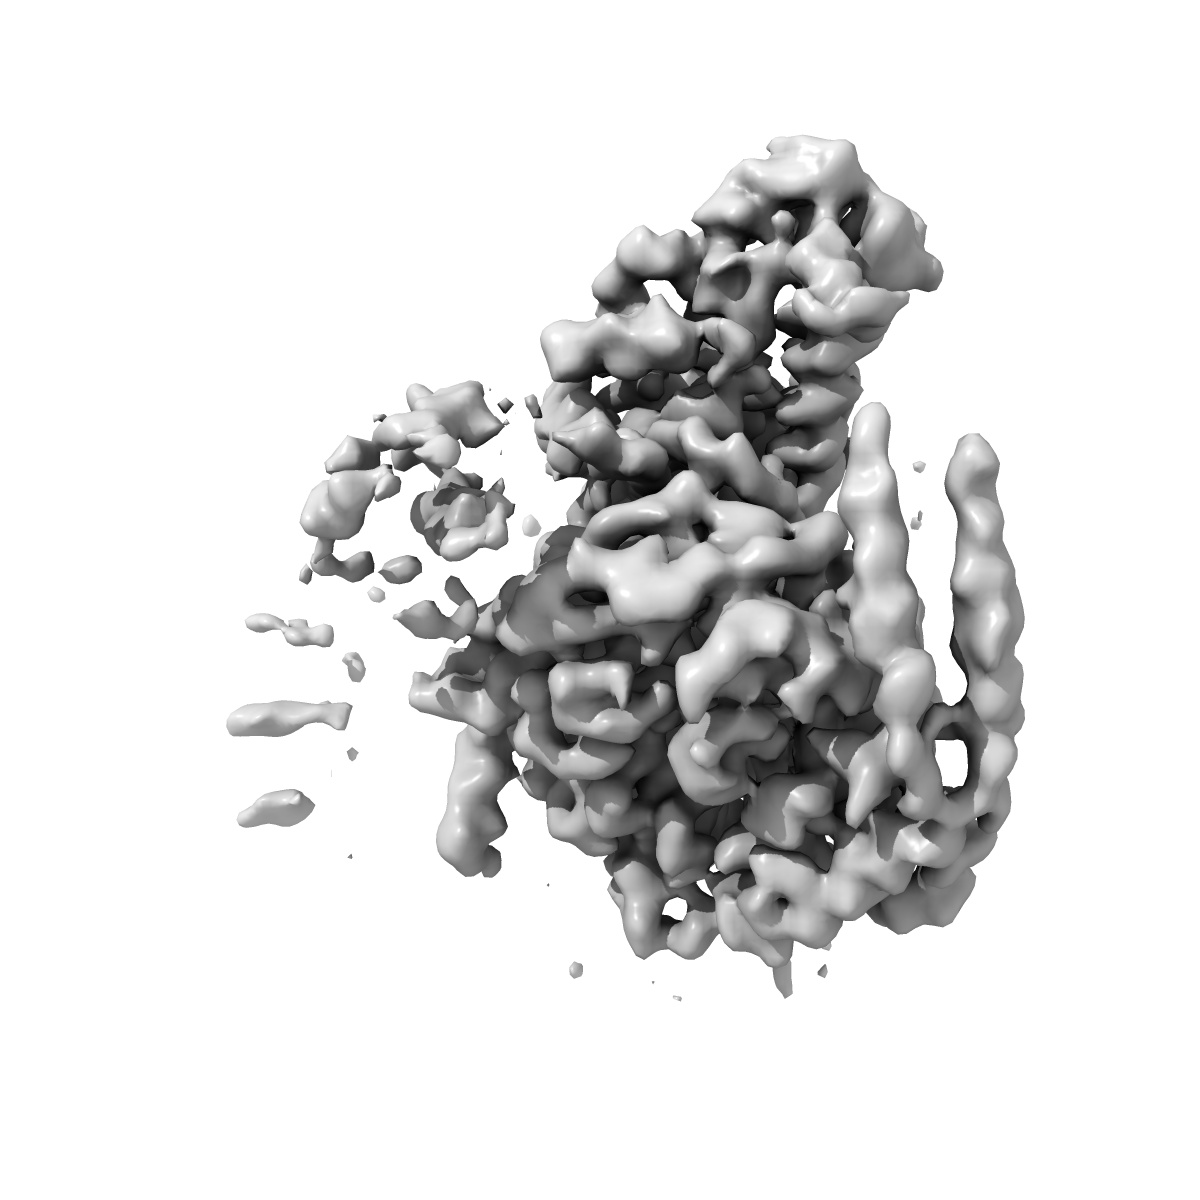

CryoEM structure of D2 dopamine receptor in complex with GoA KE mutant and dopamine

Single-particle3.28 Å

Sample: Human DRD2 in complex with heterotrimeric G protein GoA (K46E) and dopamine